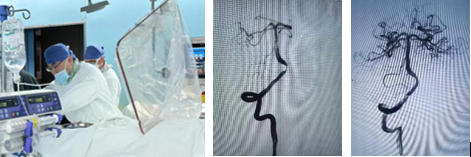

在麻手科和介入室医护支持下,在全身麻醉状态下,王亚冰教授亲自实施介入治疗。历经一小时左右,顺利完成了球扩支架治疗,检查显示狭窄和颅内供血明显改善。患者术后清醒并安返病房。该手术的完成,标志着医院颅内动脉狭窄的介入治疗迈上了新台阶。

王亚冰教授亲自实施手术及椎动脉狭窄术前、术后治疗情况